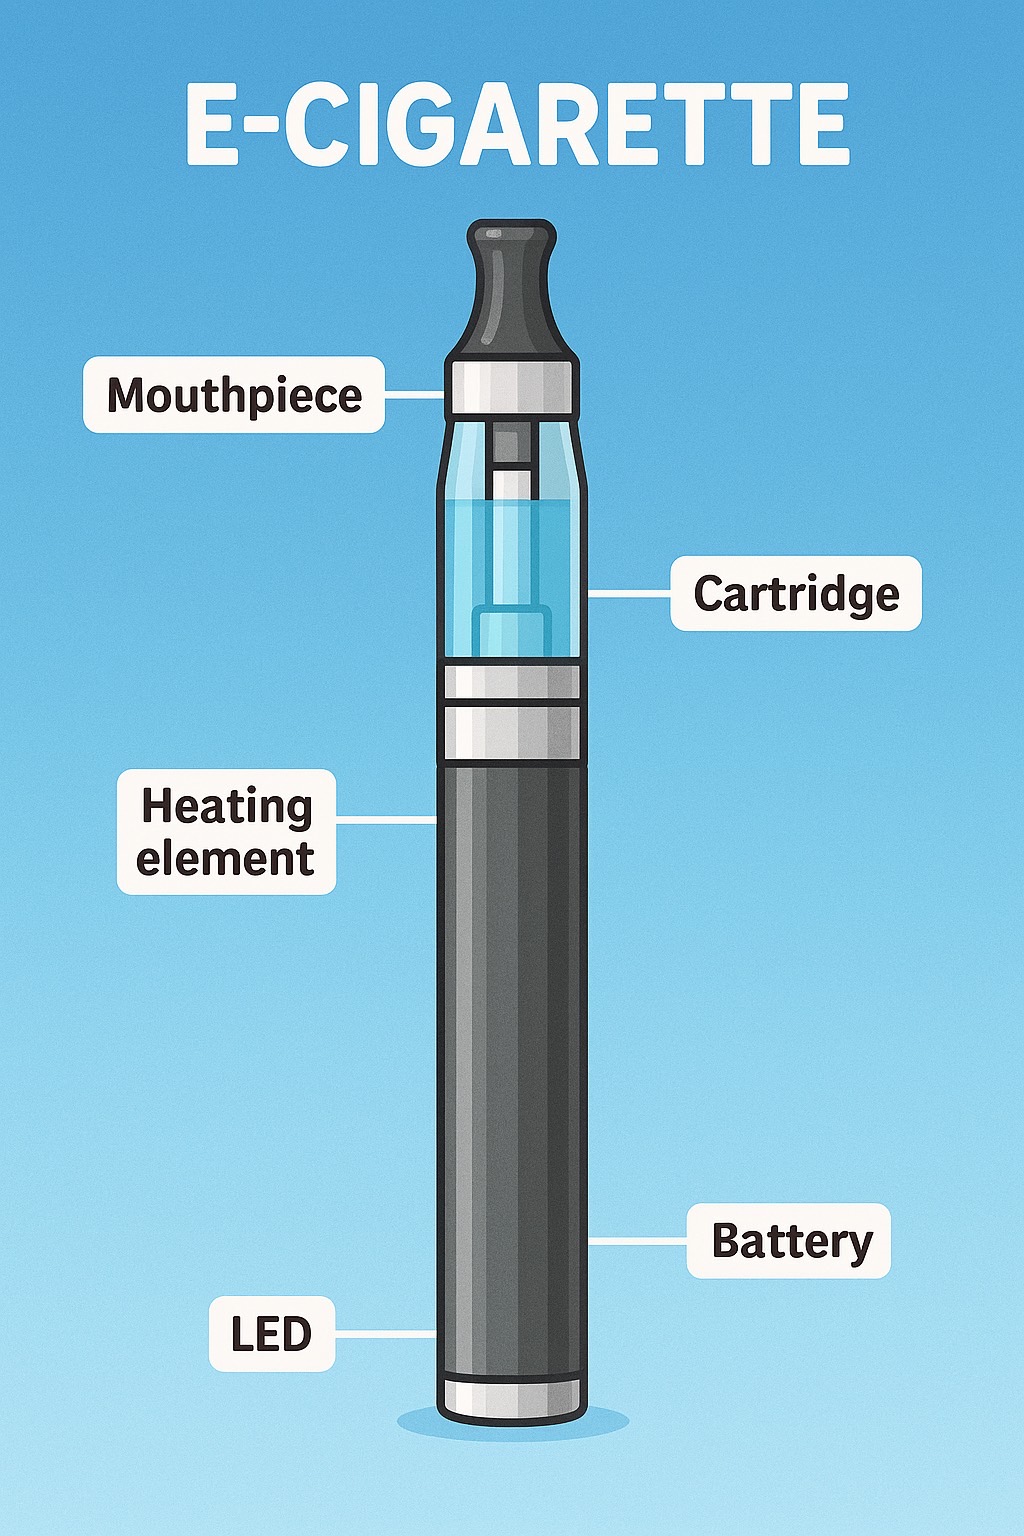

โครงสร้างของบุหรี่ไฟฟ้า

บุหรี่ไฟฟ้า (Electronic Cigarette หรือ E-cigarette) คืออุปกรณ์อิเล็กทรอนิกส์ที่ออกแบบมาเพื่อสร้างไอน้ำจากของเหลวที่มีนิโคติน และสารแต่งกลิ่น โดยส่วนประกอบหลักได้แก่:

- แบตเตอรี่ สำหรับจ่ายไฟฟ้า

- อะตอมไมเซอร์ (Atomizer) ทำหน้าที่ให้ความร้อนแก่ของเหลว

- แทงก์หรือพอด (Tank/Pod) บรรจุน้ำยา

- ปากดูด (Mouthpiece) สำหรับสูดไอระเหยเข้าสู่ร่างกาย